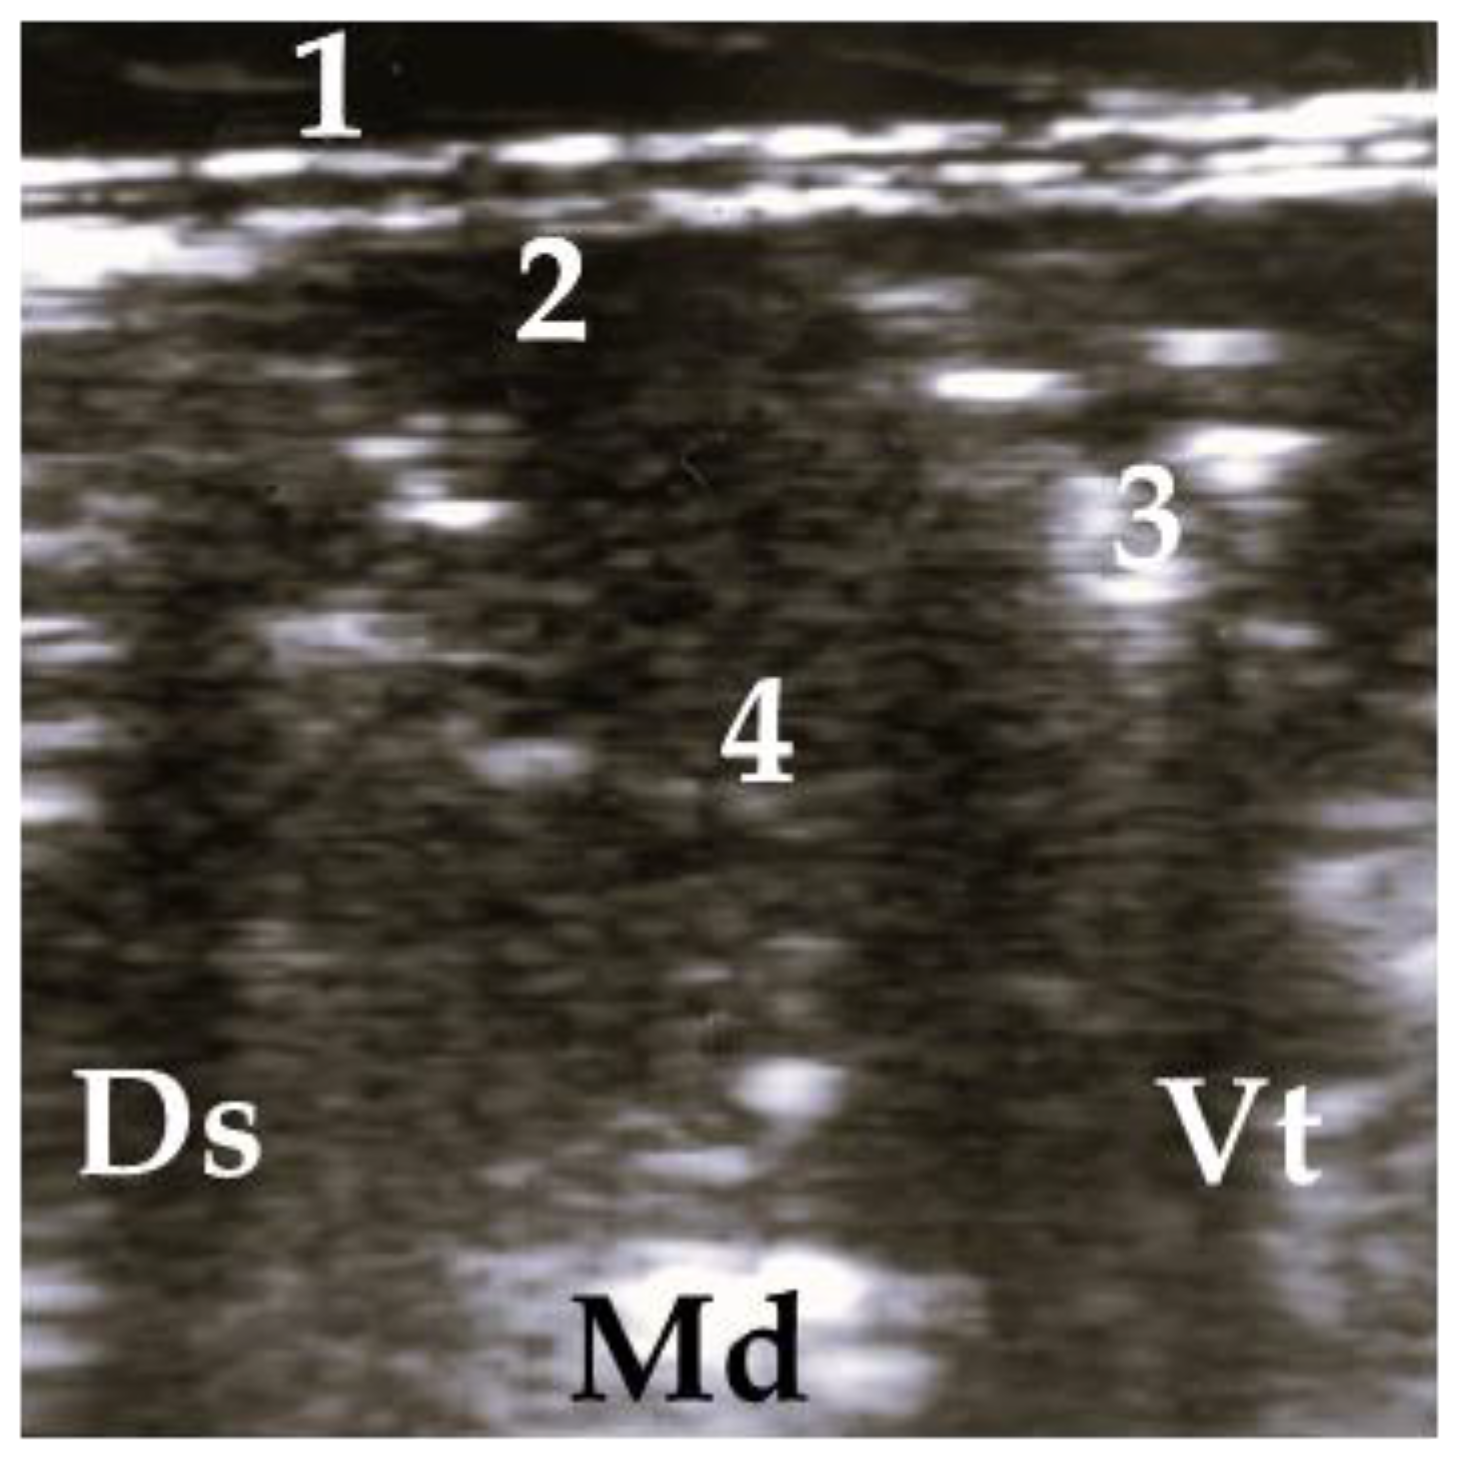

2.5. Ultrasonographic Examination

4.2. Assessment of Ultrasonographic Findings of Respiratory Disease

4.3. Association between Antemortem Physical and Ultrasonographic Examination Scorings and Scorings of Postmortem Inspection